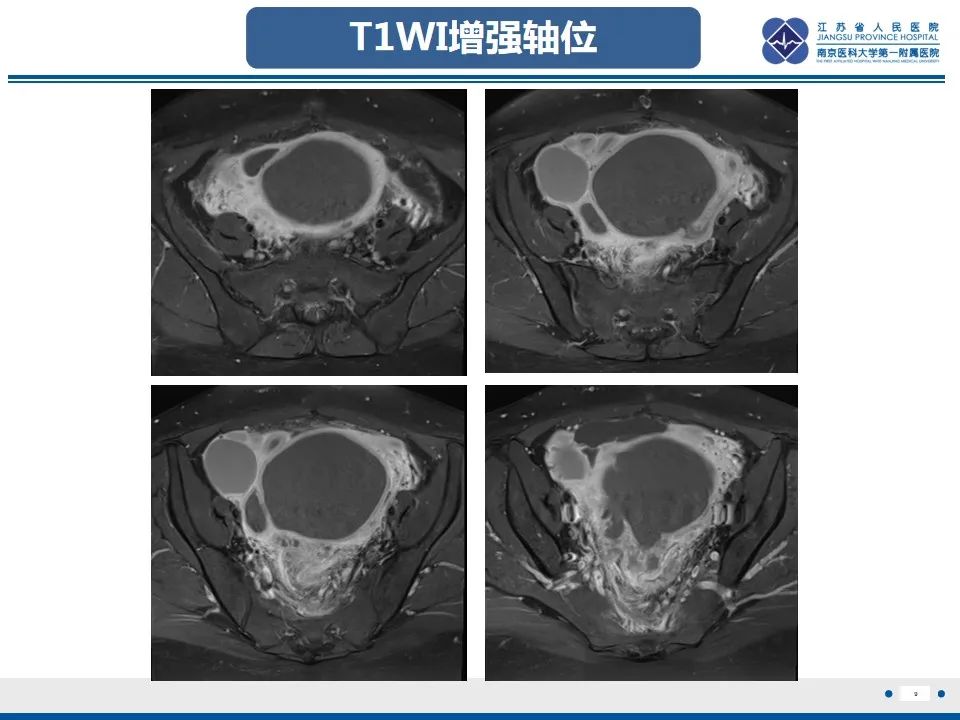

本文首发自江苏省人民医院放射科